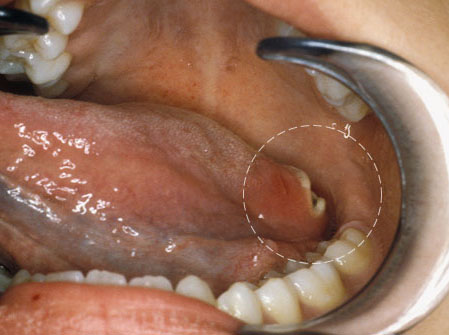

Ubushize nabasangije bimwe mu biba ngo indwara ya kanseri yibasire umubiri. Muri iyi nyandiko ndabagezaho bumwe mu buryo bukoreshwa mu gusuzuma, kuvura no kwirinda kanseri.